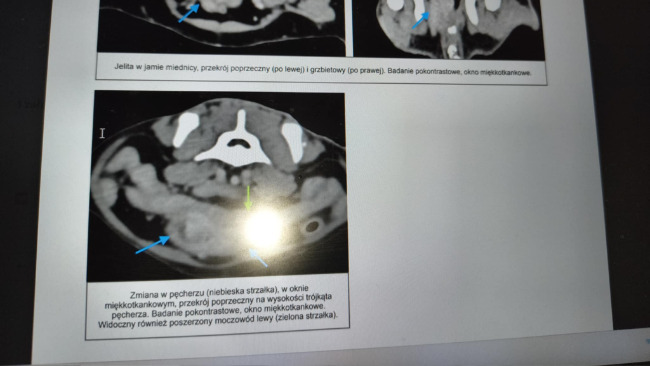

Niedawno wykonano tomografię. Wynik złamał nam serca.W pęcherzu Maxa wykryto guz. Trzeba go jak najszybciej usunąć – inaczej Max nie przeżyje....